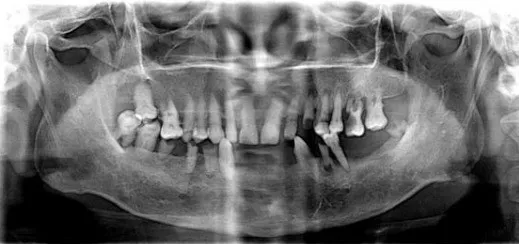

▲ 常见的牙片是二维的

然后是牙齿全景影像图和分析结果标识,哪颗牙缺失了,根尖周炎的位置,能让你比照镜子还要看的清楚自己牙齿的样子。